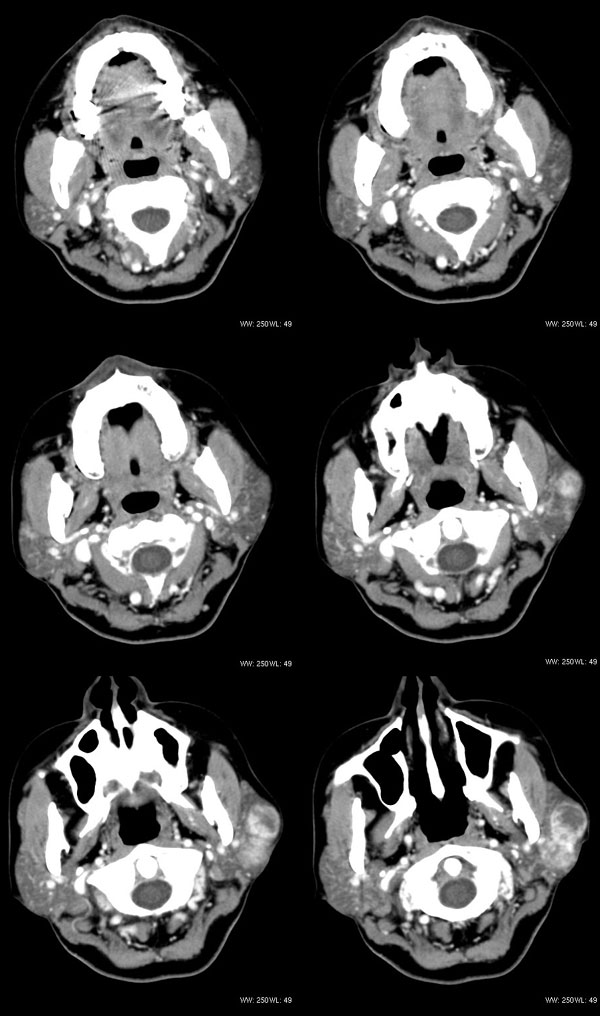

女性,43岁。左腮部肿物5年。体检:(肿物)质中,约5x4x4cm,边界清,固定。

左腮腺肿物,内可见低密度坏死区,增强扫描示肿块明显强化,且呈持续延迟强化,常规考虑腮混合瘤可能性大,但强化表现不太符合,不除外腮腺纤维血管瘤、神经鞘瘤、淋巴瘤及巨淋巴结增生症

考虑左侧腮腺混合瘤。  肿瘤较大,边清,囊变,强化明显,皮肤及淋巴结无异示

左侧腮腺多形性腺瘤可能性大。1、是混合瘤中最常见的良性肿瘤;2、中年女性多见并且时间长症状轻;3、病灶内有低密度坏死区,增强时强化;4、其内有钙化,囊性部分未强化;5、需与囊性淋巴瘤相鉴别。